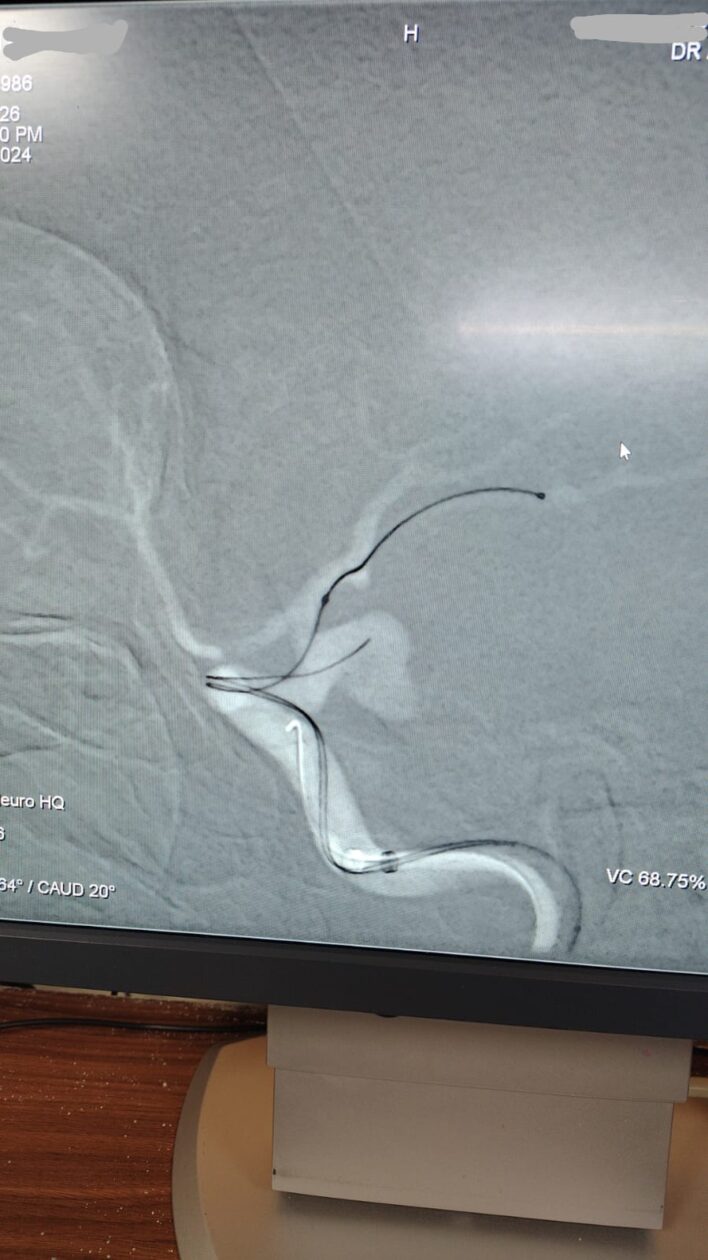

Ruptured Brain aneurysm (left ICA communicating segment wideneck aneurysm) treated with Stent Assisted Coiling.

after complete coiling and stenting